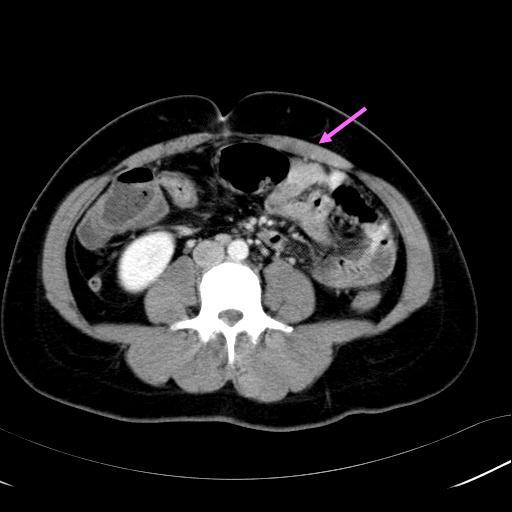

步入了中年,或許健壯不在,但還是有些線索可以辨別。

接下來這一組影像,可以好好呈現男女的差異。人都會漸漸變油,而脂肪堆積的位置會有不同。

粉紅箭頭可以發現,女生的脂肪會較大比例堆積在皮下,像是件厚厚的皮衣,在肚子裏頭的脂肪相對較少。藍色箭頭是典型的中年男性,皮下的脂肪比例較少,兒肚子裡的脂肪可是滿滿飽脹,這便是啤酒大肚的由來。